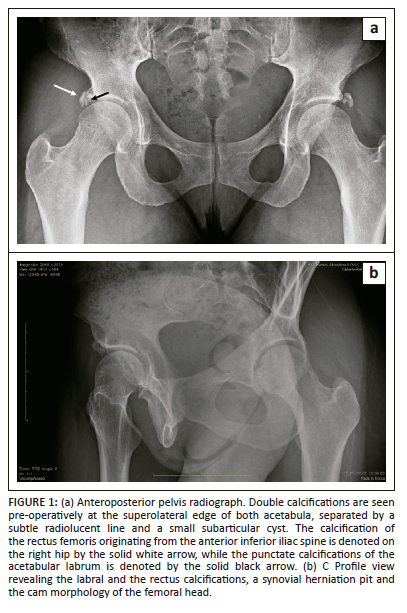

Plain radiographs of her pelvis demonstrated calcifications around the superolateral aspects of both acetabula, a synovial herniation pit, cam morphology and a small subarticular cyst (Figure 1a and Figure 1b). Upon scrutiny, the calcifications were seen arising from two distinct origins. The double calcifications were separated by a subtle radiolucent line, with the calcification of the rectus femoris being round and originating from the anterior inferior iliac spine, while punctate and amorphous calcifications of the acetabular labrum were observed to arise beneath the superolateral rim of the right acetabulum. Similar calcifications were also observed on the contralateral left hip. For other relevant hip imaging parameters, the lateral centre edge angle of the right hip was 30°, the alpha angle was 69°, the Tonnis angle was 8°, and the articular space was normal. Advanced imaging was obtained via MR arthrogram of the right hip, revealing rupture of the anterior-superior labrum with early chondral delamination. The patient was informed of her diagnosis of right hip femoral acetabular impingement (FAI) with chondrolabral rupture and rim calcifications and was advised on surgical intervention in the form of right hip arthroscopy.